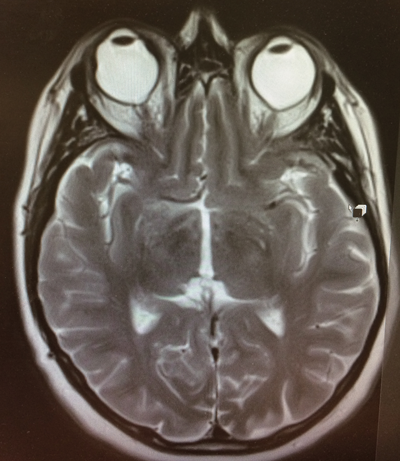

On her return to the UK, she first presented to our hospital three months after the operation with a painful right 3mm proptosed eye that showed an elevated area nasally with some subconjunctival blood underneath. Her VA was 6/24 with correction. The swelling came and went at intervals over the next few weeks and there were also episodes of external bleeding from it (Figure 1). The B-Scan showed that the haemorrhage also spread around the encircling band nasally and the MRI did not point to masses in the orbit nor to scleral thickening or any intracranial abnormalities (Figure 2).

Figure 2: T2 weighted MRI brain and orbits scan in the transverse plane

shows a proptosed right bulbus secondary to the encircling band.